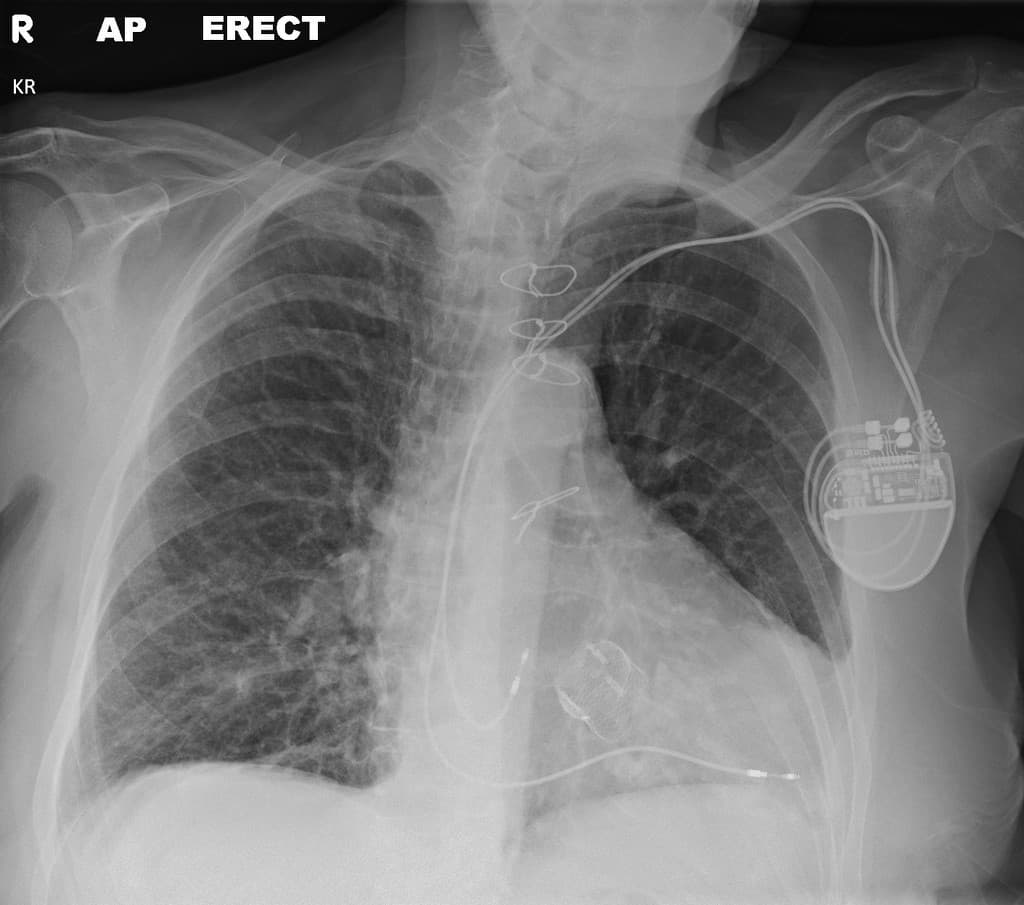

Chụp X-quang ngực kiểm tra trước khi chụp MRI (Pre-MRI check chest x-ray).

- Máy tạo nhịp tim (cardiac pacemaker) nằm ở vùng ngực trái với các đầu dây dẫn (lead tips) ở vị trí phù hợp. Không thấy các dây dẫn bị bỏ lại (abandoned leads).

- Ghi nhận TAVI tại vị trí dự kiến của gốc động mạch chủ (aortic root). Một giá đỡ lòng mạch (stent-graft) có hình dạng tương tự nằm ở cung động mạch chủ (aortic arch).

- Thể tích phổi thấp với các đường mờ dạng lưới (reticular markings) tăng lên, phù hợp với (consistent with) tình trạng xơ phổi (pulmonary fibrosis) đã biết.

- TAVI nằm ở vị trí phù hợp tại gốc động mạch chủ (aortic root). Một TAVI thứ hai được nhìn thấy nằm kẹt ở cung động mạch chủ (aortic arch).

THẢO LUẬN (DISCUSSION): Xem xét hồ sơ bệnh án điện tử của bệnh nhân đã xác nhận tiền sử tuột van (dislodgement) và thuyên tắc (embolization) TAVI tại thời điểm cấy ghép, sau đó một TAVI thứ hai đã được cấy ghép thành công.